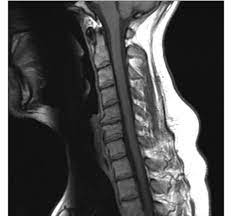

- 자기 공명 영상 (MRI): MRI 스캔은 목 부위의 디스크와 주변 조직을 자세하게 보여줍니다. 디스크의 헤르니에이션, 디스크 디게너레이션, 신경 굴곡 등을 평가하는 데 주로 사용됩니다.